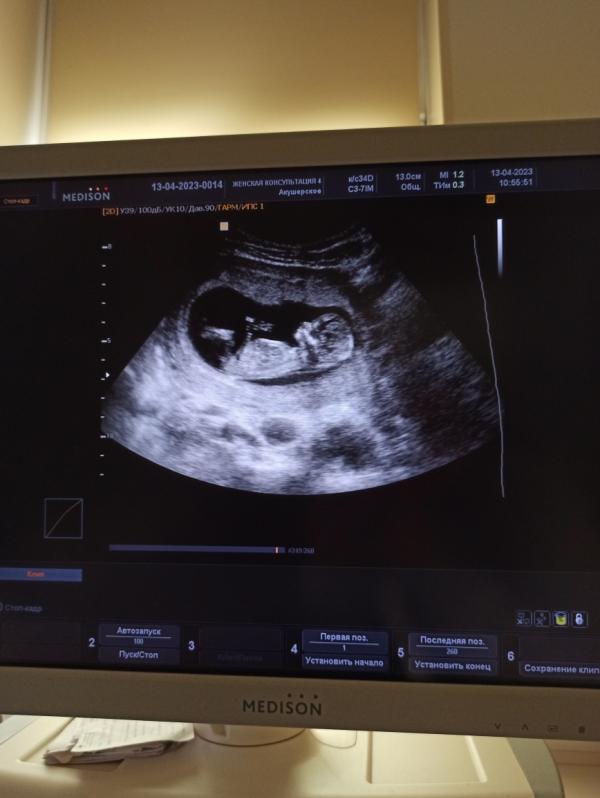

Прошла первый скрининг, с малышом всё хорошо, размер соответствует сроку!

Очень похоже на девочку💕

Кроха всего 6 см по ктр)

Ждём в 20 х числах октября😊